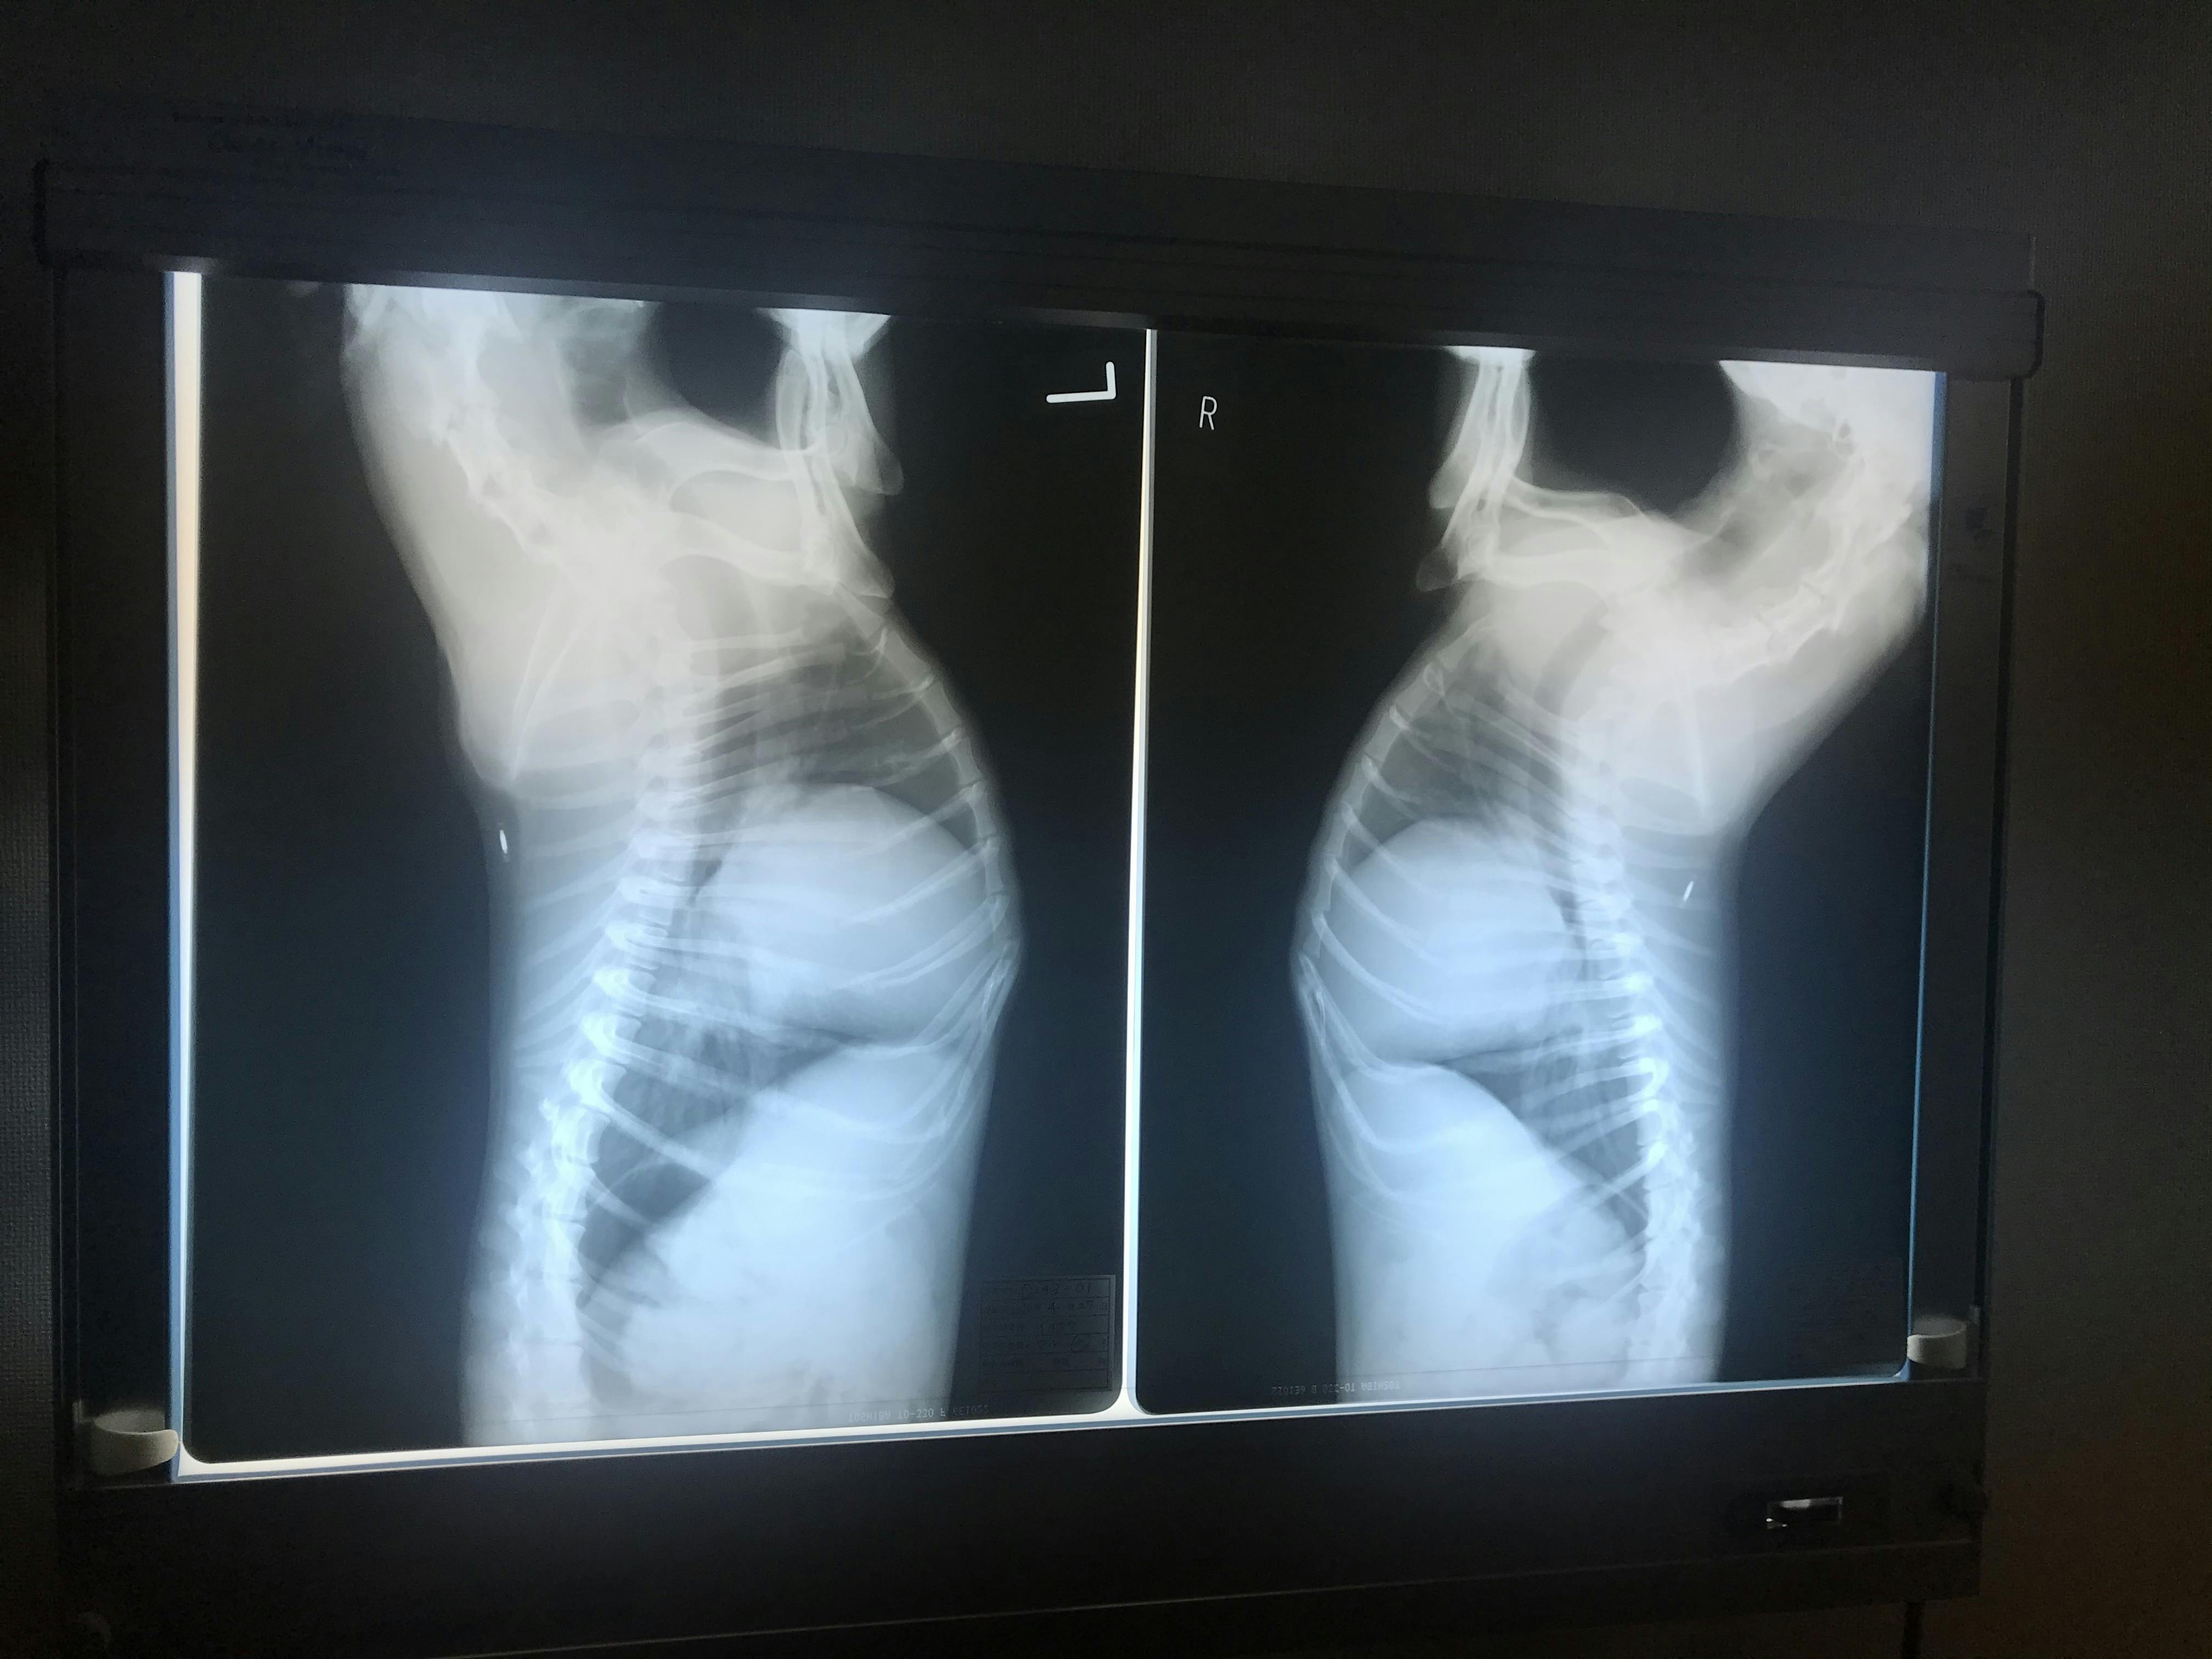

2020.04.27 コロナ禍のため、いつも通っている病院ではなく近場の病院へ行ってきました。レントゲンは撮りましたが専門医ではないため、エコーは出来ず。薬もジェネリックのものしかもらえないという顛末に…

レントゲンを見れたことはよかったです。